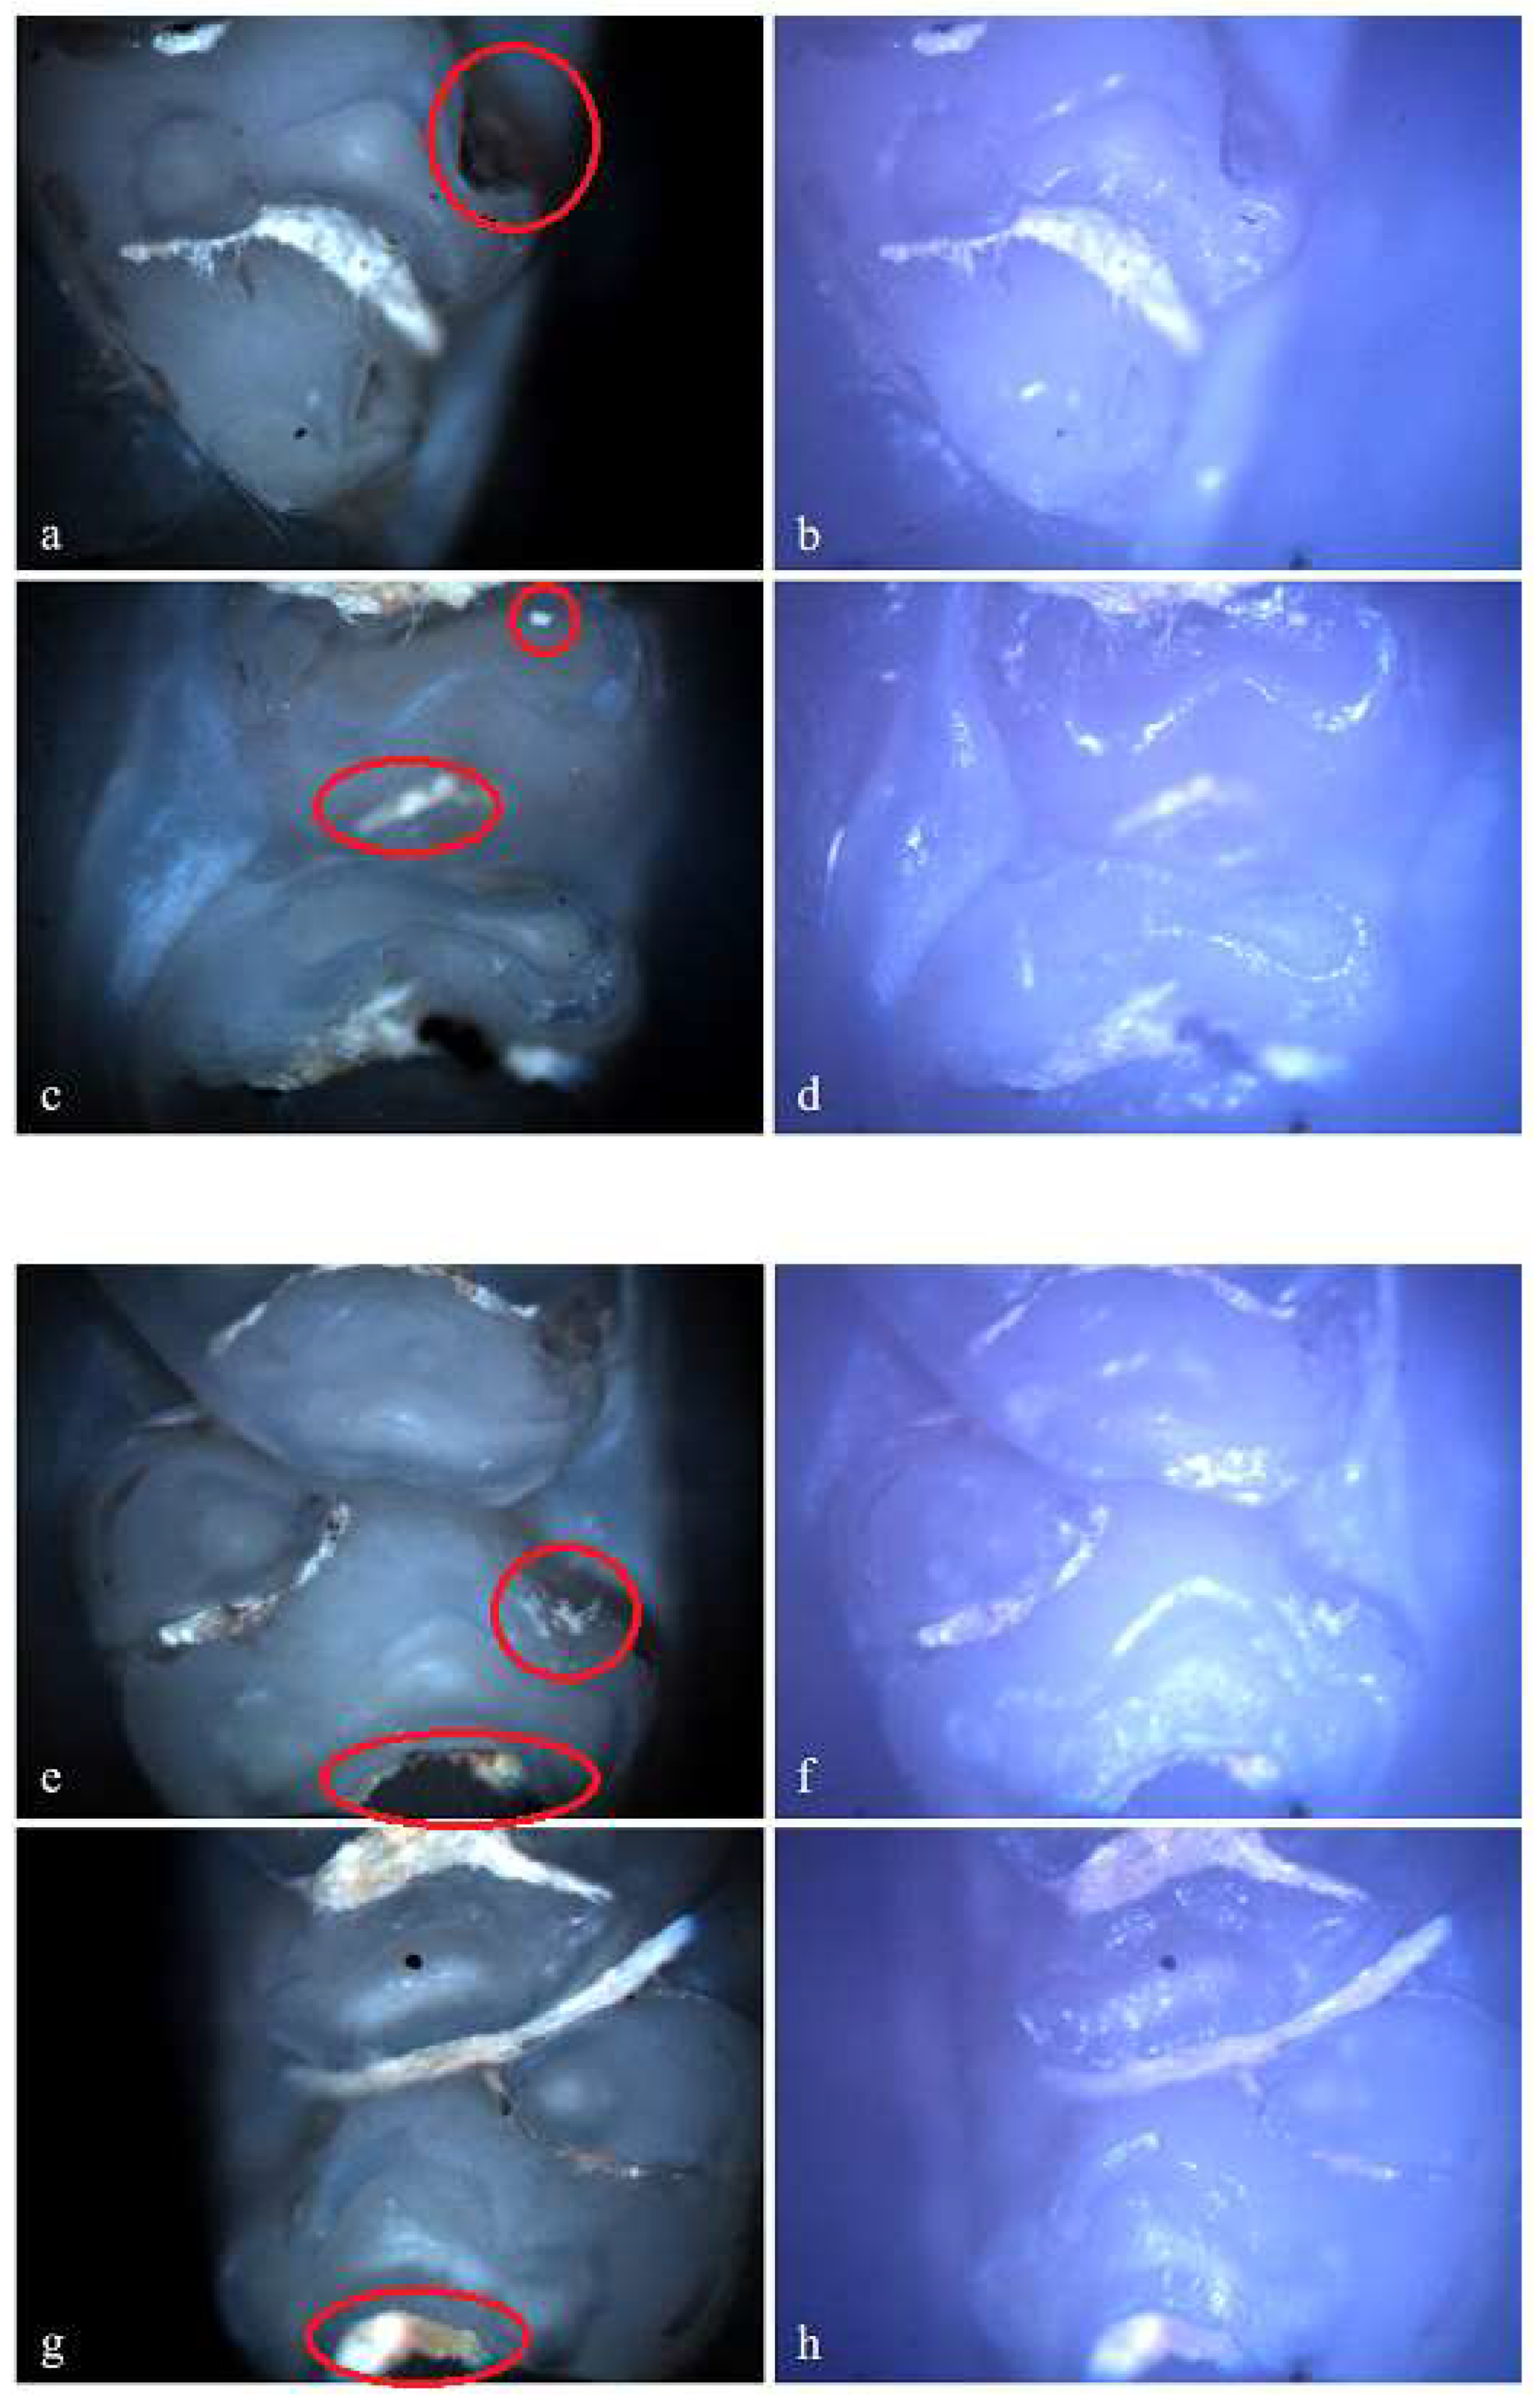

Figure 9. Demineralization on the occlusal surface of some molars (a, c, e - Polarized microscopy image, 4X objective; b, d, f - Optical microscopy image, 4X objective) and on the mesial surface of a molar (g - Polarized microscopy image, 4X objective; h - Optical microscopy image, 4X objective).

In the standard dose ibuprofen group (8 mg/kg), 11 rats (73.33%) showed at least one clinical form of DDE. Of these, 2 rats showed hypoplasia and 5 rats showed demineralization. Also, 3 rats showed both clinical forms of DDE. Within this group, from a total number of 240 teeth, 33 teeth (13.75%) presented at least one clinical form of DDE, respectively 15 incisors (45.45%) and 18 molars (54.55%), and according to the clinical form of DDE, 7 teeth (21.21%) showed hypoplasia (molars) and 26 teeth (78.79%) showed demineralization (15 incisors and 11 molars). Each tooth with DDE had only one affected surface, resulting in a total of 33 affected tooth surfaces.

Figure 10. Demineralization on the occlusal surface of some molars (a, e, i - Polarized microscopy image, 4X objective; c, g, k - Polarized microscopy image, 10X objective; b, f, j - Optical microscopy image, 4X objective; d, h, l - Optical microscopy image, 10X objective).

In the standard dose cefaclor group (20 mg/kg), 14 rats (93.33%) showed at least one clinical form of DDE. Of these, 5 rats showed demineralization and 7 rats showed both clinical forms of DDE. Within this group, from a total number of 240 teeth, 45 teeth (18.75%) presented at least one type of DDE, respectively 20 incisors (44.44%) and 25 molars (55.56 %), and as a clinical form of DDE, 15 teeth (33.33%) showed hypoplasia (2 incisors and 13 molars) and 30 teeth (66.67%) showed demineralization (18 incisors and 12 molars). Among the 45 affected teeth, 10 teeth showed DDE on 2 surfaces, resulting in 55 affected tooth surfaces.